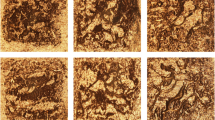

Method optimization for tissue sectioning

Cutting undecalcified bone tissue without embedding resulted in shattered fragments. Therefore, embedding bone tissue proved necessary to maintain sample integrity during sectioning. In a previous study, gelatin and CMC has been used as embedding materials for chicken digits [10]. Chicken digits differ from rat and mouse bone, the latter being harder and more brittle. An optimal embedding material and sectioning protocol for undecalcified bone tissue of rats and mice focusing only on MALDI-MSI has not been determined yet. Three different embedding media were tested with different concentrations of CMC to maintain the integrity of the sample. Of these embedding media, 7.5% proved to provide the best sections, while 10% CMC showed to exceed the solubility threshold. Tissue sections were visually assessed by a light microscope to evaluate their integrity. Optimal section parameters were chosen based on a surface homogeneity. As the embedded samples still shattered during sectioning, double-sided tapes were used to increase the support. The section thickness and temperature were optimized for each of the four tapes. Optical images of a section obtained with different tapes are shown in ESM Fig. S1. The Tesa® tape gave the most homogenous sections. The final workflow for the sample preparation and MALDI-MSI measurements for undecalcified bone tissue is shown in Fig. 1.

Here, we present a sample preparation protocol for undecalcified bone tissue developed and optimized for analysis with MALDI-MSI. Embedding in an aqueous solution of 20% gelatin (w/v) and 7.5% carboxymethyl cellulose (CMC, w/v) in combination with the use of double-sided tapes proved to be necessary to maintain sample integrity during sectioning. It is of utmost importance to avoid bubbles of any kind (air, water from melting crystals in tissue) in the medium during embedding of the tissue. Bubbles will result in holes in the embedding which cause less support during sectioning and thus low-quality sections, while at 60 °C, the embedding material is poured in a mold. The tissue sample is immersed immediately. As a result, the frozen sample will start melting. It is recommended to immediately start polymerization after sample embedding by freezing at − 20 °C to avoid tissue degeneration due to the heat. Only the tungsten carbide knife was found to be robust enough to cut bone tissue without permanent deformation of the blade. Different amounts of CMC were tested. The amount of CMC was increased compared with that in previous studies to ensure a smooth transition from embedding to bone tissue while sectioning. Increased amounts of CMC gave more homogenous sections with less relief compared with lower CMC concentrations. Above 7.5% (w/v), the solution was saturated and CMC could not dissolve anymore. Still the sections were not completely homogenous. An embedding medium with characteristics closer to those of bone tissue would have been even better, but this medium still has to be MSI-compatible, making conventionally used resins unsuitable. For example, other research groups use tragacanth or SCEM-L1 embedding medium for sectioning bone tissue [7, 26]. Unfortunately, tragacanth is hygroscopic, making it not fit for use after storage in a freezer. On the contrary, the gelatin/CMC-embedded samples could be easily reused for at least 5 times after storage. Samples were stored in aluminum foil and frozen at − 20 °C or − 80 °C. Although the gelatin/CMC mixture is MS-compatible, it has the disadvantage of being used at higher temperature than the frozen tissue during embedding, which can cause heat stress and/or affect the molecular composition of the bone [11].

Four different double-sided tapes were evaluated for suitability, specifically two non-conductive normal tapes and two conductive tapes. When choosing a tape as a support during sectioning, different parameters should be taken into consideration. The first one is the capability of the tape to stick to the frozen gelatin/CMC block. While the temperature affects the adherence of the tape, it is important to have a good adherence to the frozen sample to create a homogenous sample. As a result, the adherence will determine the optimal temperature for sectioning as well as the thickness of the sections. A tape with a good adherence makes it possible to generate thinner sections. In addition, the thickness of the sections should be considered carefully. On one side, a thin section will give less insulation and hence a higher overall signal intensity. On the other side, thinner sections also mean that less analyte will be available for extraction into the MALDI matrix and subsequent desorption [1]. Thicker sections will take more time to dry in the desiccator. It is noteworthy that some mass spectrometers, such as linear ToF, conductive samples/tape, and therefore the tape selected here, would be unsuitable. The double-sided Tesa® tape resulted in the most homogenous sections at a thickness of 12 μm.